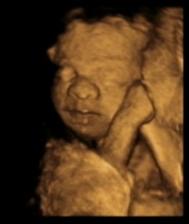

Dne 11.3.2009 nastal den D a já našla na těhotenském testu znovu // čárky. S manželem jsme si jisti, že tentokrát to dopadne dobře a my se konečně dočkáme našeho vytouženého zlatíčka.

Broučka jsme se opravdu dočkali. Dne 25.10.2009 v 19.24 hod. přišel předčasně na svět (35 tt). I když se narodil dříve, je to čiperka a má se čile k světu. Jmenuje se Matyášek a je to naše velké zlatíčko.